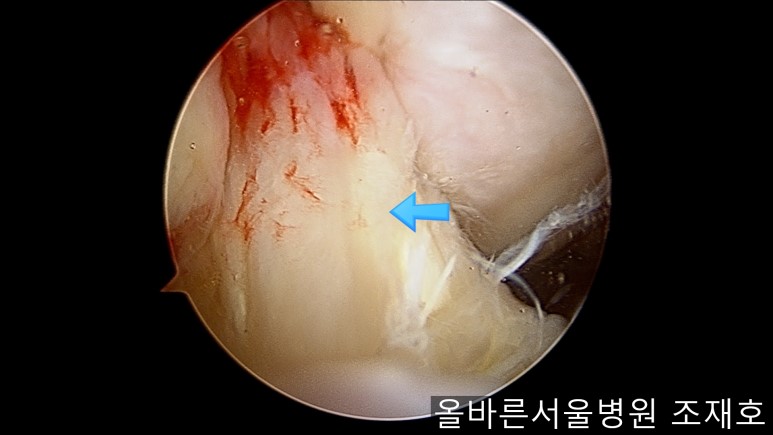

为了软骨再生,在胫骨上端进行微骨折术。

胫骨上端是通过微骨折术,可再生软骨的地方。

尽量将孔打地细密,确认此处骨髓腔内的血流出。

在股骨部位用CARTISTEM注射用4mm激光钻细密打孔,并确保软骨板不倒塌。不用切开通过关节镜即可完成手术。

如图,尽量细密打孔。